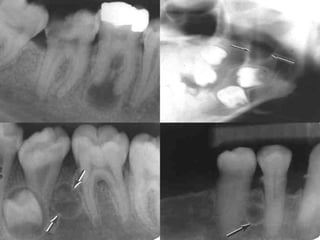

 The lesion appears as a well-delineated radiolucency with a

radiopaque border.

 When the radiolucency is adjacent to the roots of teeth, it has a

scalloped appearance extending between the roots. The teeth are

not displaced, and the lamina dura and periodontal ligament space

appear intact.

 If the lesion occurs in areas not associated with the roots of teeth,

the well-defined radiolucency may be round or ovoid.

 Radiographic features:

 Small well circumscribed radiolucent

area with definite border and surrounded

by a thin layer of sclerotic bone at the

apical or lateral surface of the root,

usually less than 1 cm in diameter.